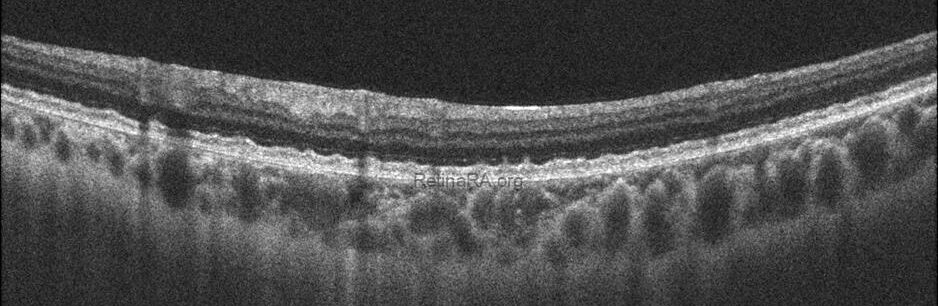

Optical coherence tomography (OCT) provides valuable structural information in fundus albipunctatus. OCT imaging typically demonstrates focal hyperreflective material originating from the RPE and projecting into the outer retinal layers, correlating with the punctate lesions seen on fundus examination. On fundus autofluorescence imaging, a diffusely reduced background autofluorescence is commonly observed, reflecting impaired retinoid metabolism and RPE dysfunction related to disruption of the visual cycle.